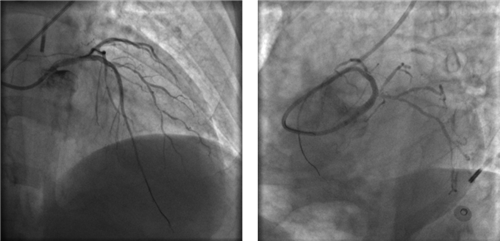

左主干完全閉塞

小心操作導(dǎo)絲及導(dǎo)管,艱難到達(dá)主動脈根部,但導(dǎo)管難以“到位”左冠口,“冒煙”見左主干居然完全閉塞了。

右冠近段嚴(yán)重狹窄,未見右向左的側(cè)枝循環(huán)

再行右冠造影,右冠近段也嚴(yán)重狹窄,未見右冠向左冠的側(cè)枝循環(huán)。

球囊擴(kuò)張后,左冠血流恢復(fù),但左主干末端重度狹窄

左主干末端呈三分叉,前降支、回旋支均存在彌漫性病變,且血管非常細(xì)小,這是一個相當(dāng)復(fù)雜的左主干分叉病變。冒然植入支架,可能導(dǎo)致支架邊緣夾層、分支閉塞、慢血流等并發(fā)癥,稍有不慎,都會給患者帶來災(zāi)難性的后果。心血管內(nèi)科團(tuán)隊慎重決定,暫不植入支架,在IABP支持下,待血流沖刷冠狀動脈,血管痙攣解除、血管擴(kuò)張后,再在IVUS(血管內(nèi)超聲)指導(dǎo)下植入支架。

左冠血流保持通暢

確認(rèn)左冠血流保持通暢,大家懸著的心才稍稍放下。

根據(jù)IVUS檢查結(jié)果,在前降支近中段至左主干植入3枚支架,充分?jǐn)U張后,狹窄完全解除,血流恢復(fù)通暢。

植入3枚支架,血流恢復(fù)通暢